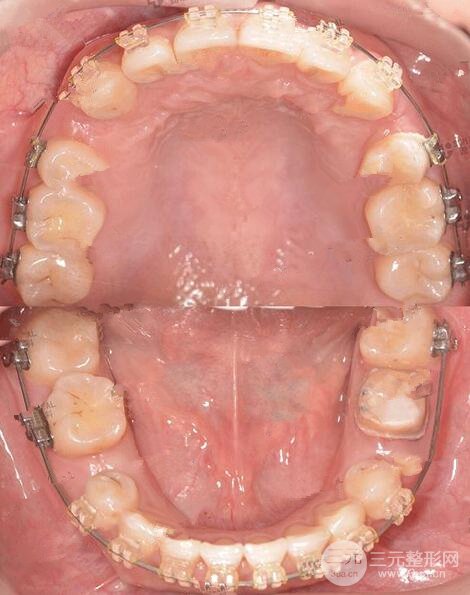

這是拔除四顆雙尖牙后 原本不對(duì)稱的牙弓現(xiàn)在已經(jīng)對(duì)稱 中線也調(diào)整到正常位置

現(xiàn)在還在排齊階段拔牙間隙已經(jīng)變小很多,后期我們繼續(xù)整平牙弓,就可以完全關(guān)閉拔牙間隙調(diào)整咬合了,我的左下第(一)恒磨牙是做過根管緩解的,現(xiàn)在在重新制作臨時(shí)牙套,再繼續(xù)正畸緩解。